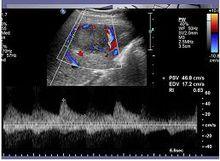

彩色都卜勒超聲(color Doppler flow imaging, CDFI)顯病灶中央有粗大的動脈向四周呈放射狀,動脈血流速高而阻力低為FNH的特徵性表現。